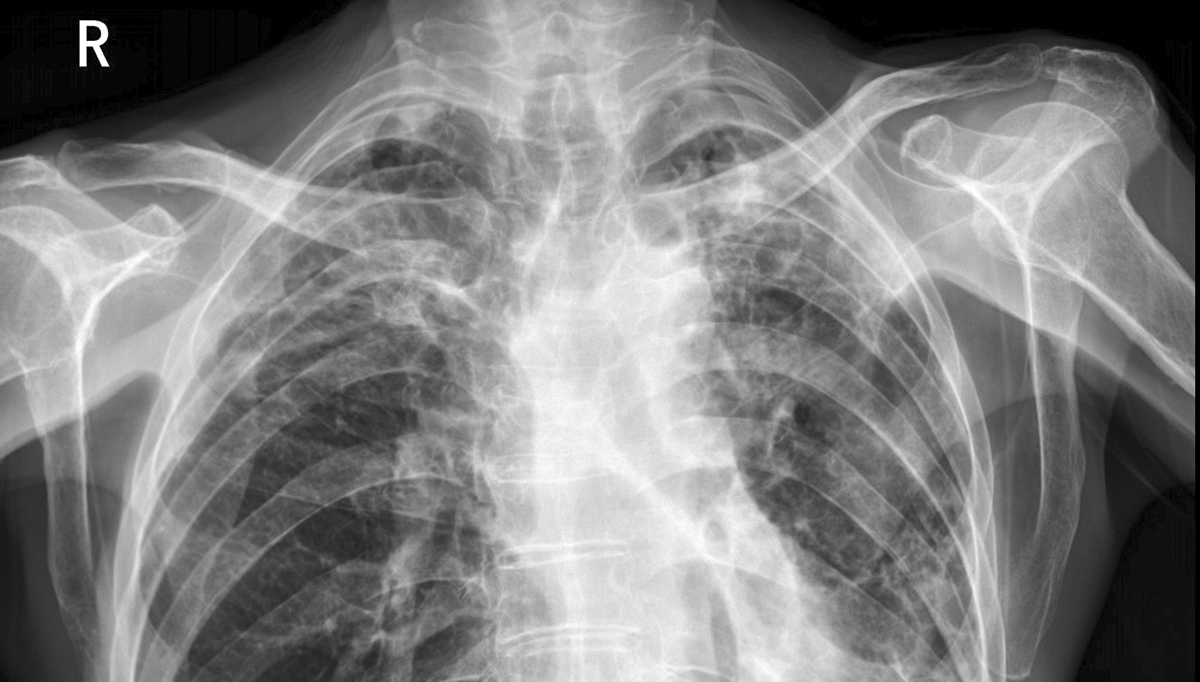

灰阶是医用显示屏呈现影像明暗层次的核心指标,直接决定软组织、病灶边界等细节的可见度。16bit灰阶意味着显示屏可呈现65536级明暗梯度,而普通8bit医用显示屏仅能显示256级灰阶。在肺部小结节诊断中,16bit显示屏能清晰区分结节与周围肺组织的密度差异,哪怕是0.5mm的微小病灶也无所遁形;而8bit屏可能将相近密度区域“合并”,导致漏诊风险。

放射科影像的动态范围极广,从骨骼的高密度区域到血管的低密度影像需同时清晰呈现。16bit灰阶医用显示屏的动态范围可达4000:1以上,能精准捕捉从强光区域到阴影部分的所有细节。以肝癌增强扫描影像为例,它既能清晰显示强化的肿瘤病灶,也能完整呈现周围肝实质的细微变化,为分期诊断提供全面依据。